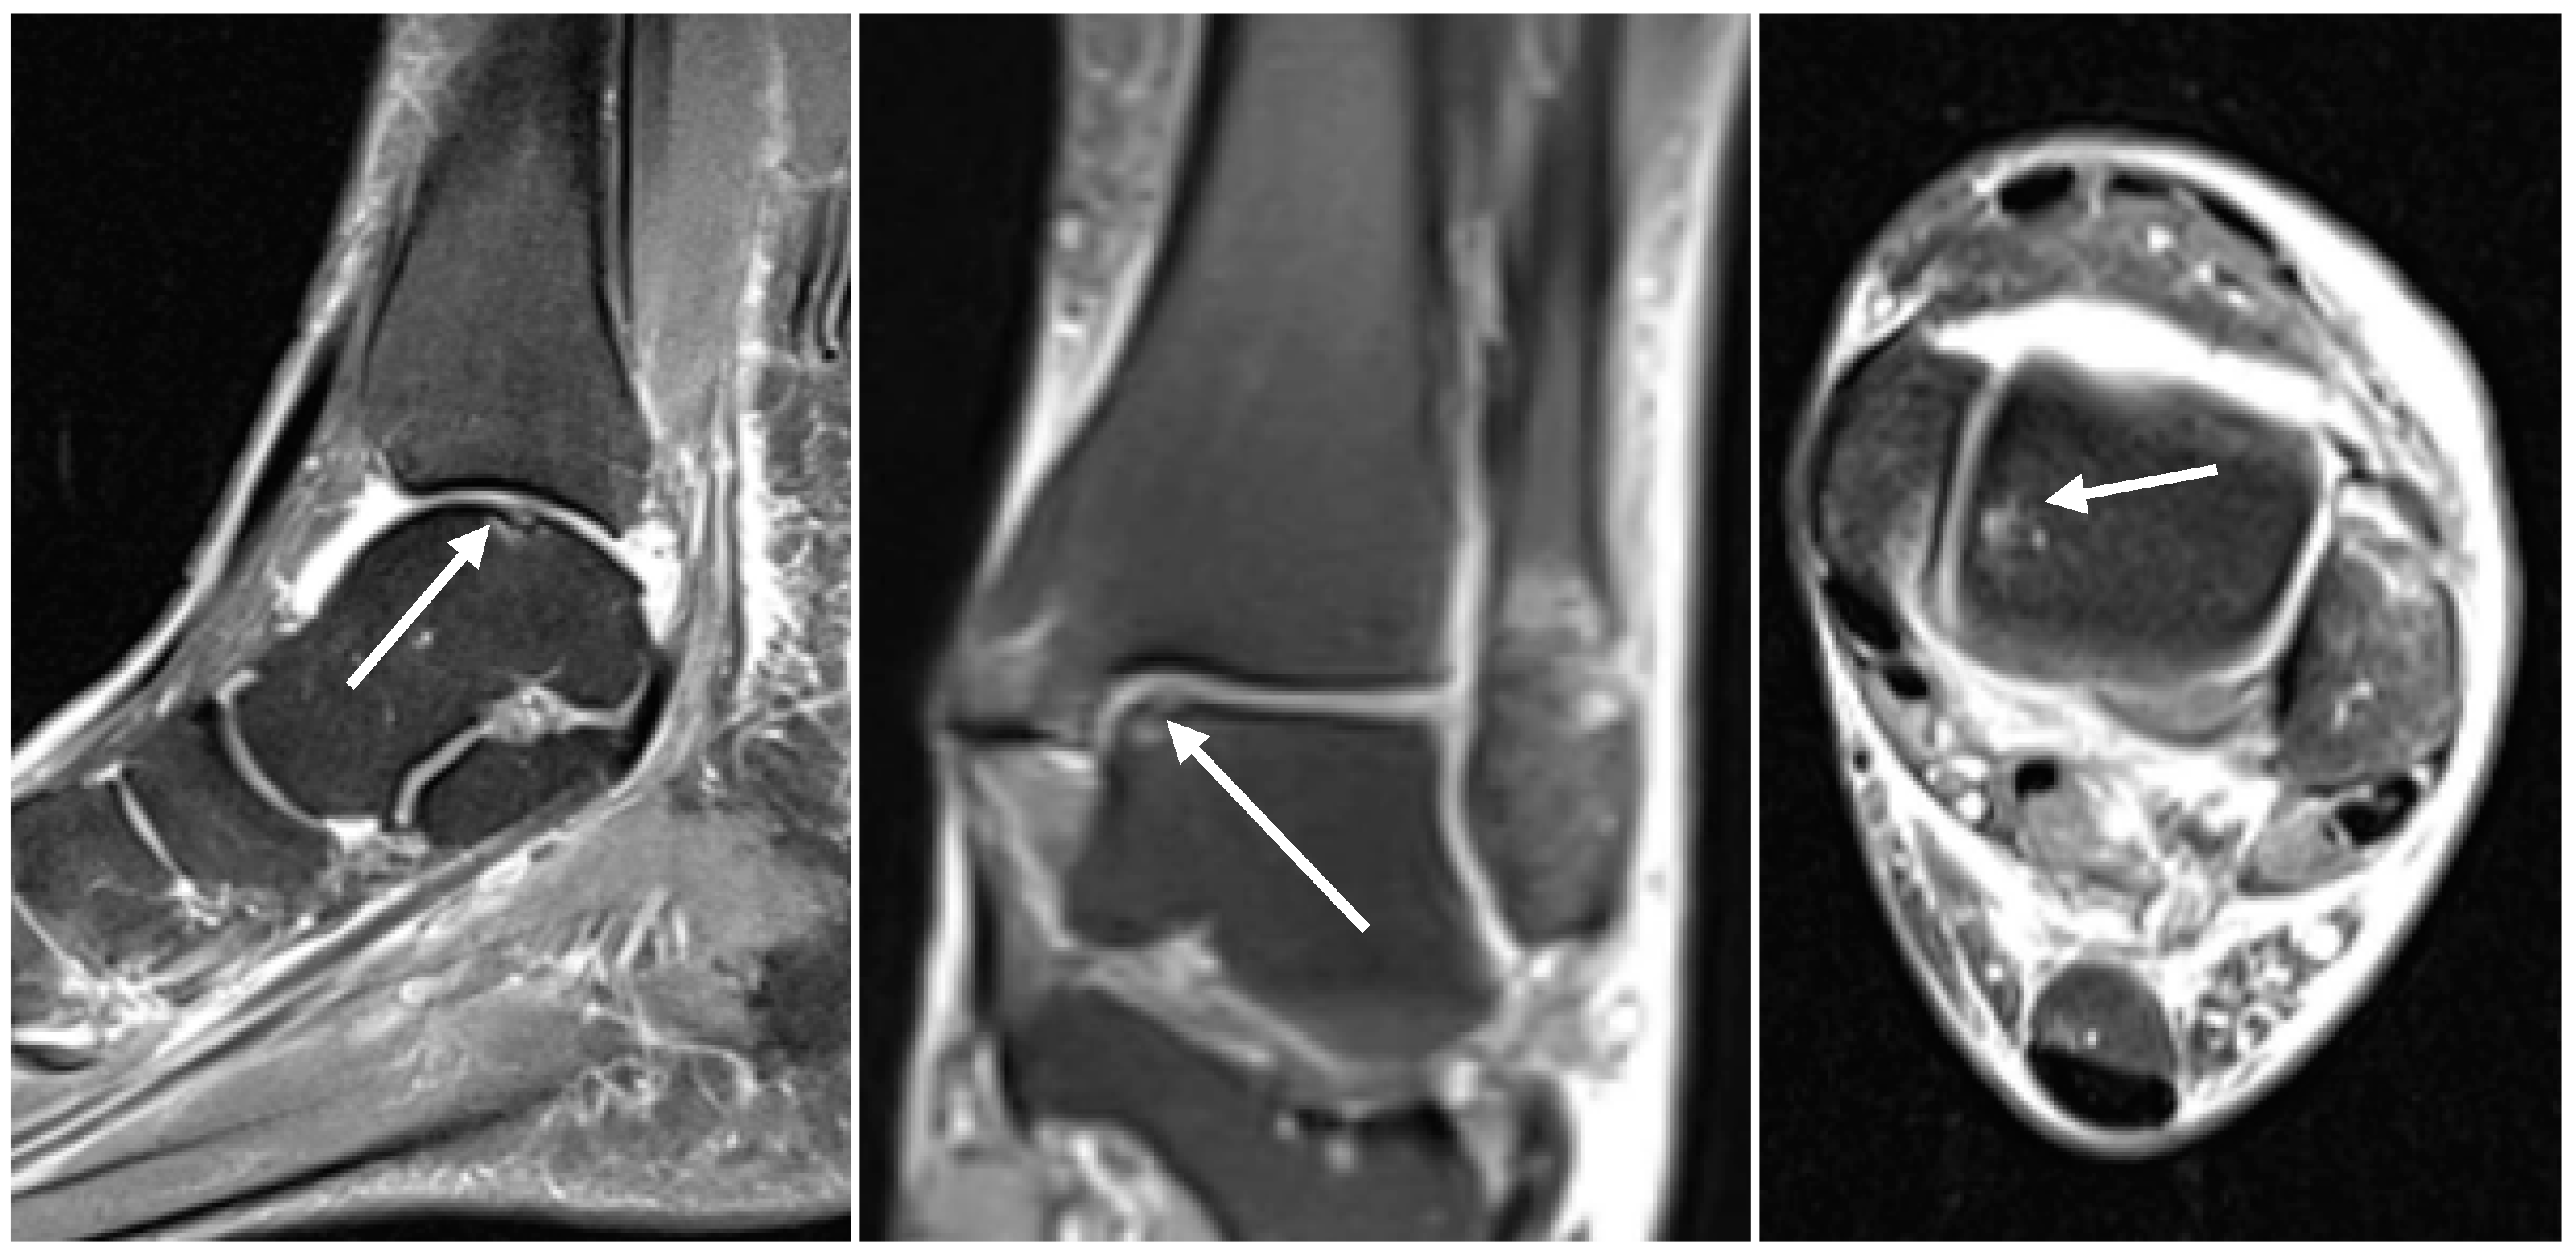

2.2. Radiological Assessment

3.1. Assessment of the Preoperative MRI Scans

3.2. Evaluation of the Intraoperative Arthroscopic Findings